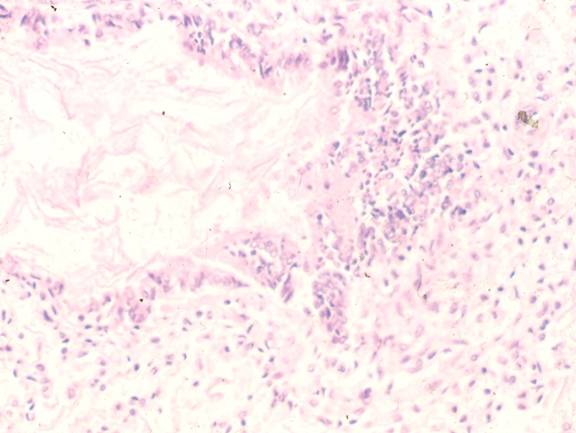

MAS 时MAS和血管的研究结果

(Thurren et al: Am J Obs Gyn 176:967-975)